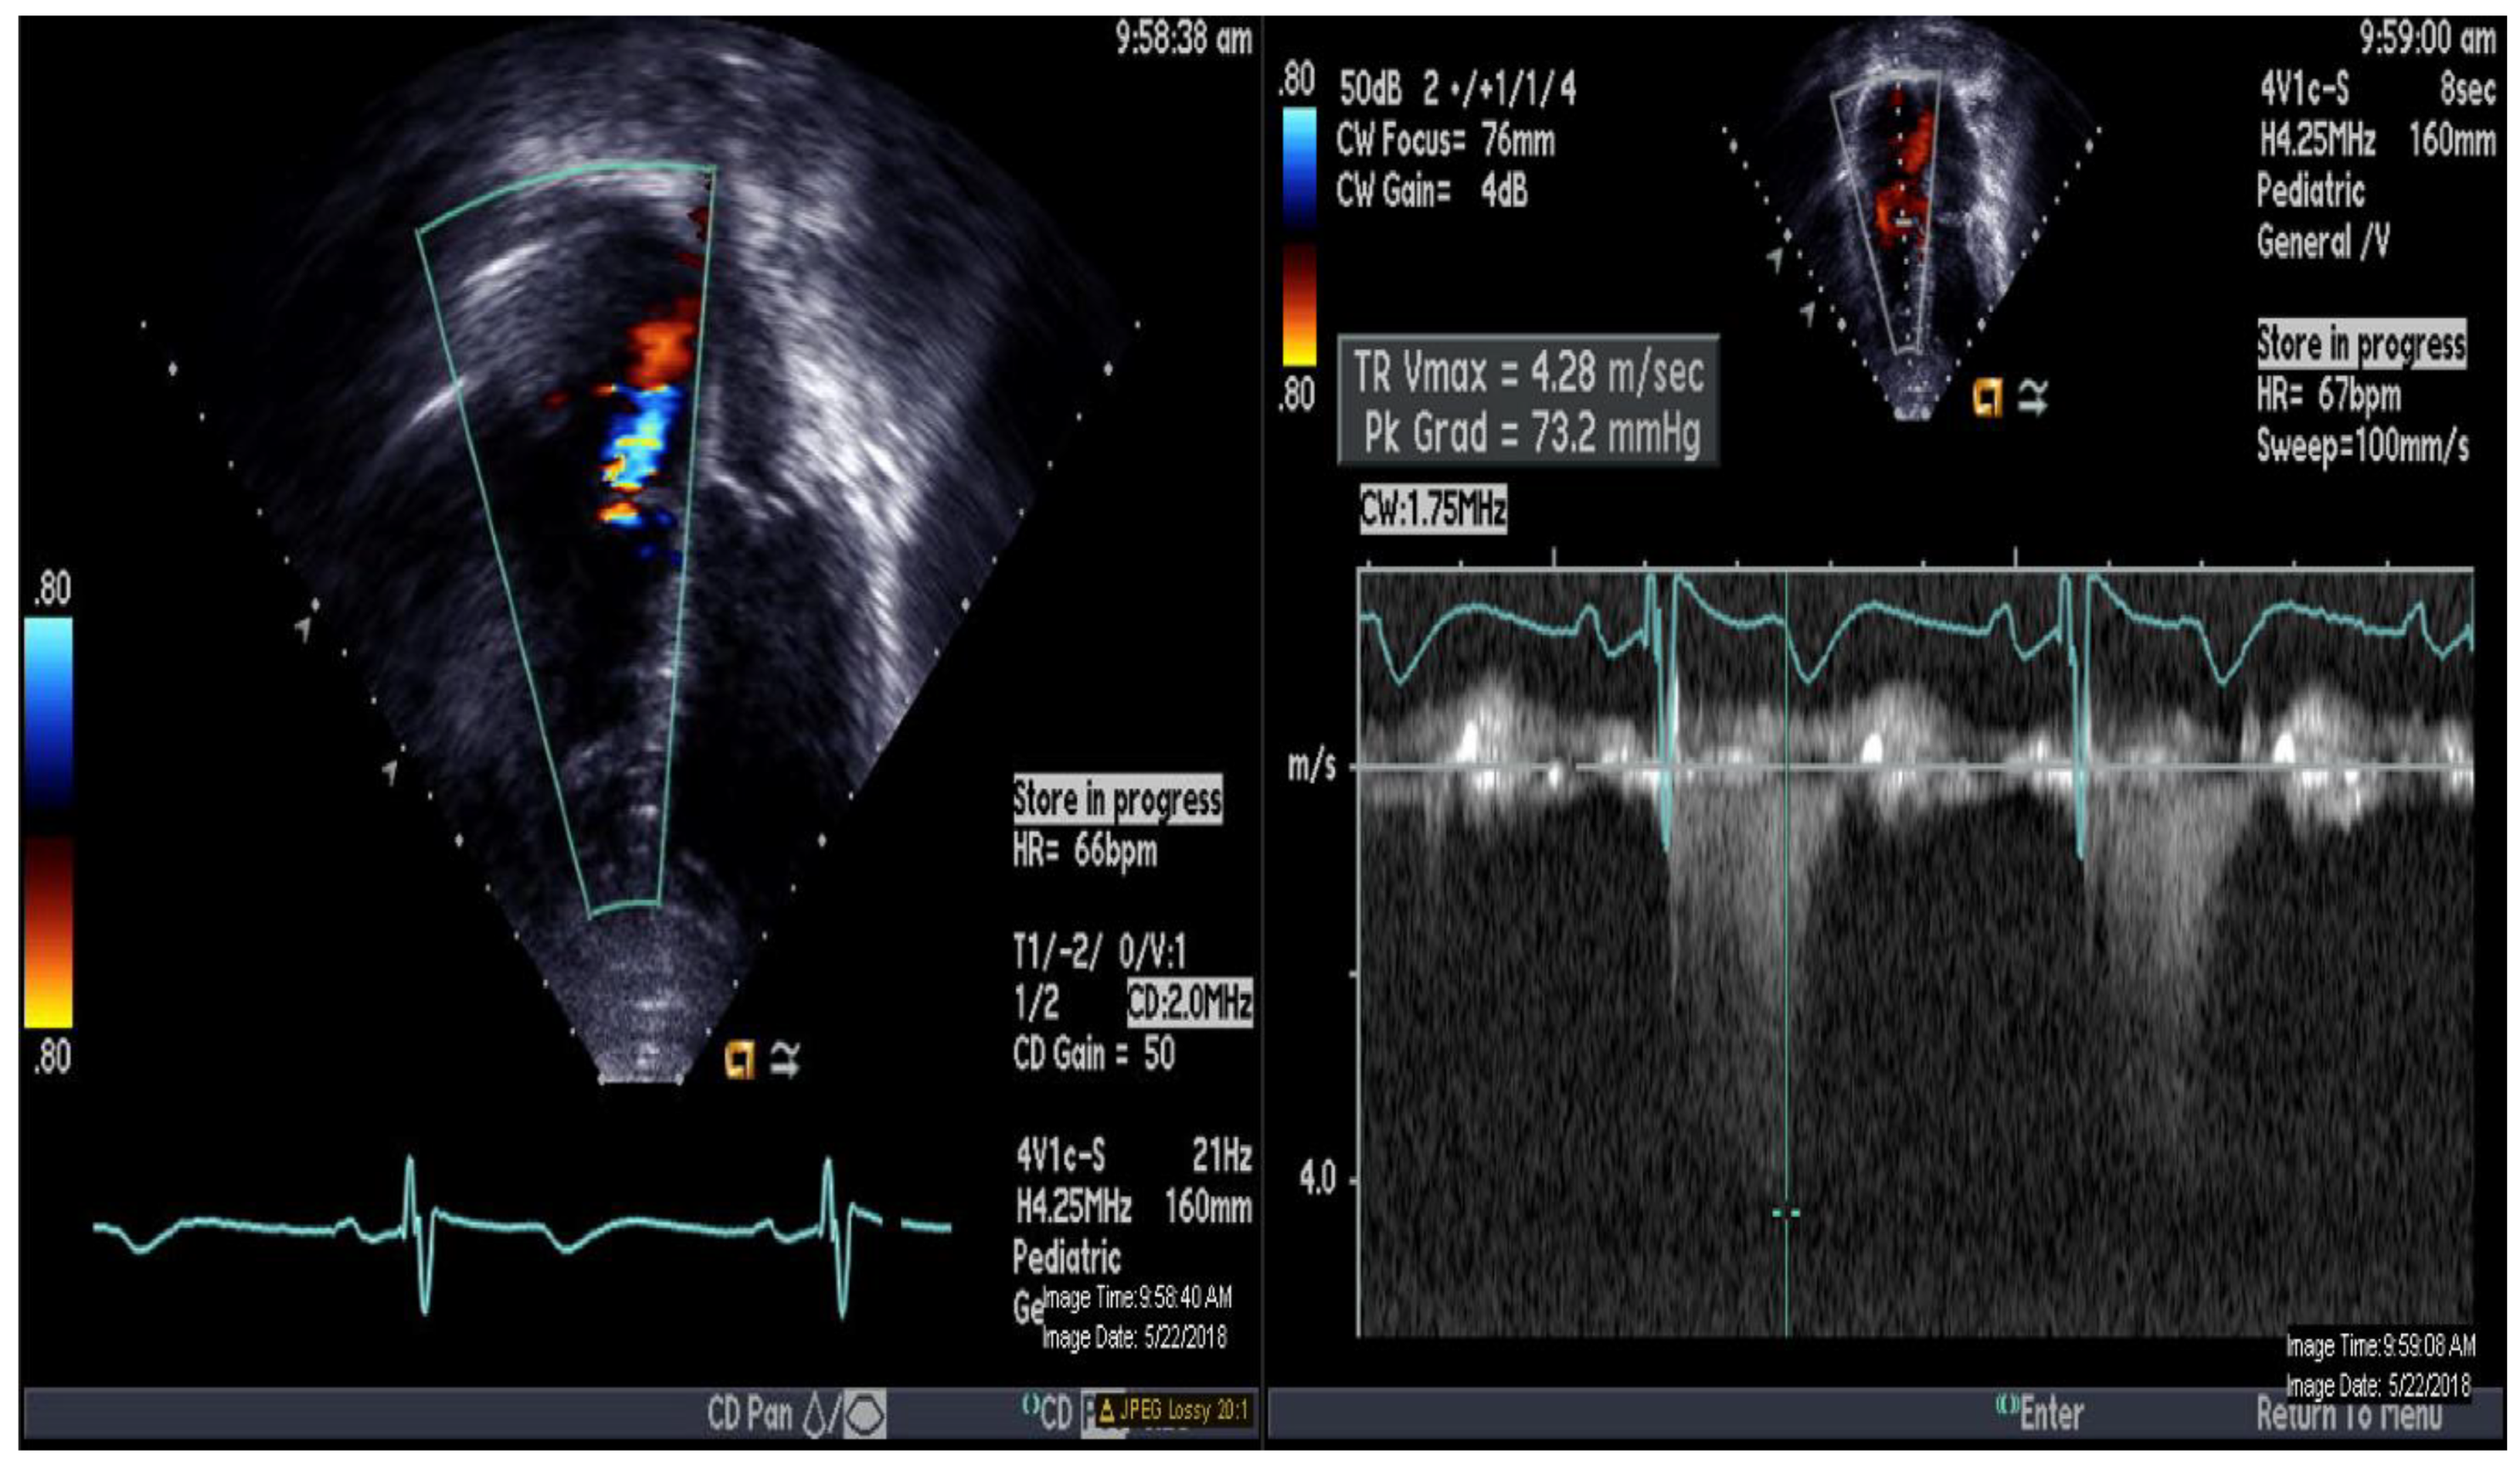

A 16-year-old adolescent boy, trisomy 21 with multiple cardiac shunts (VSD, and PDA) and echocardiography-estimated RV systolic pressure 73 mm Hg plus right atrial pressure based on tricuspid regurgitation jet (Figure 1). He was considered inoperable due to bidirectional shunting across VSD (Figure 2) by echocardiography and referred to our institution for evaluation. He underwent CMR-guided RHC and pulmonary vasodilator testing in the Phillips Ingenia 1.5 Tesla MR/catheter hybrid laboratory suit (Figure 3). The hybrid Cath-CMR setting and iCMR procedural details at Children’s Medical Center, University of Texas Southwestern Medical Center, was described previously [4].

Figure 1.

Echocardiography demonstrating apical 4-chamber view with color and continuous Doppler of tricuspid regurgitation jet.